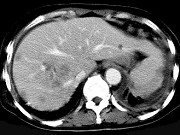

男,42岁,中上腹痛,轻度黄疸,结合CT图像,提出最可能的诊断 ( ) XH-26761.jpg XH-26762.jpg XH-26763.jpg

题型: 单选题 分类: 肿瘤放射治疗学

• A.肝脓肿

• B.肝多发性囊肿

• C.肝癌肝内转移伴门脉癌栓形成

• D.胆管细胞癌

• E.肝血管瘤